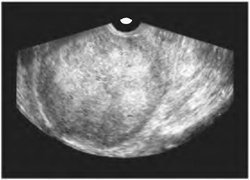

A hüvelyen scan. Erősen differenciált méhnyálkahártya adenokarcinóma

Hüvelyi méh hosszanti leolvasó. méhnyálkahártya-adenokarcinóma

Hüvelyi ultrahangvizsgálatok manysik. A rosszul differenciált endometriális adenokarcinóma, minden réteg a csírázó test falának